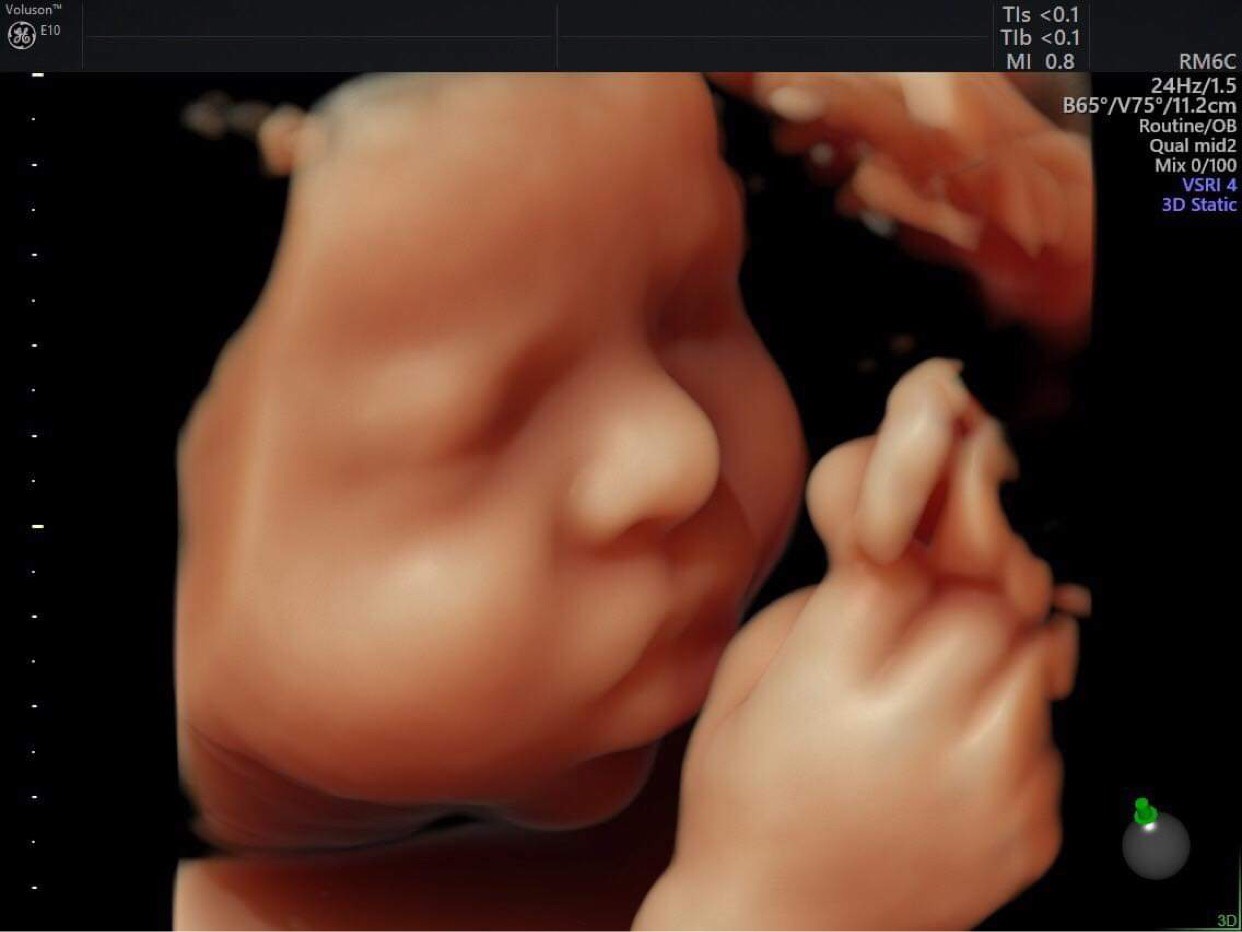

– Từ hình thức siêu âm 4D, mẹ có thể nhìn thấy khuôn mặt, làn da, tay chân cùng những chuyển động của thai nhi trong bụng, giống y như bé đang ở trước mặt mẹ vậy.

– Thông qua kỹ thuật siêu âm 4D, bác sĩ chẩn đoán, phát hiện các dấu hiệu bất thường của thai nhi như: Dị tật bẩm sinh, đa thai, hở hàm ếch, các dị tật về não … từ đó có hướng giải quyết sớm và hiệu quả nhất bảo vệ sức khỏe mẹ và thai nhi.